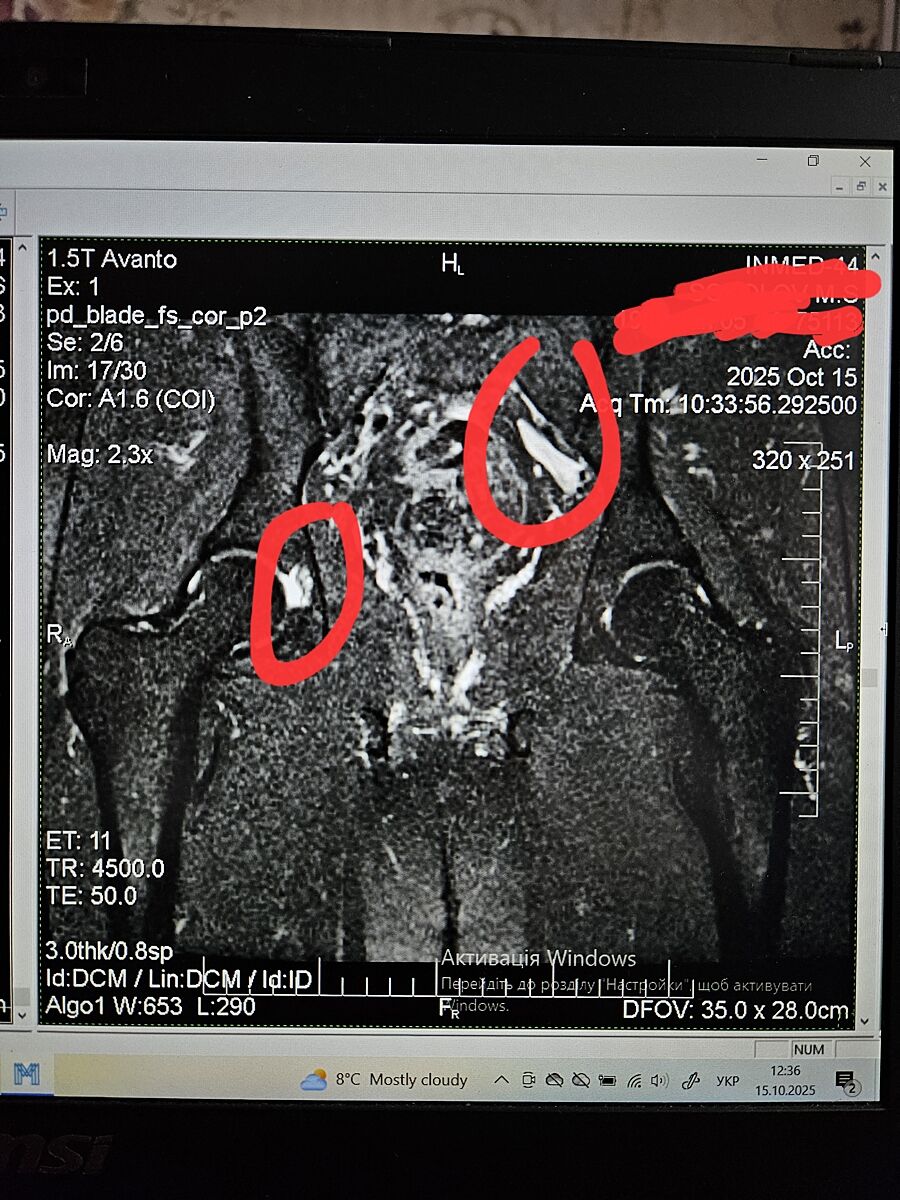

Кто-то разбирается в снимках мрт?

Пока ждем описание стало интересно что могут означать эти белые зоны.. может кто-то понимает в этом что-то?

Таз мужчины 43 года